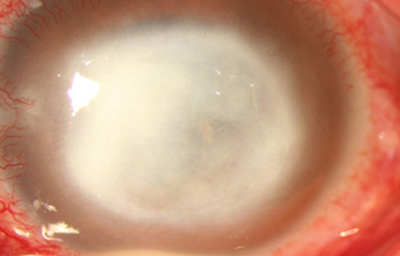

En los estados avanzados con abscesificación y queratolisis, se enmascara el cuadro corneal, ocultando las características clínicas típicas de la queratitis por Acanthamoeba. (Fig 18)

En su evolución se observará aumento del edema, agrandamiento y coalescencia de los infiltrados formando un anillo, (Figura 9, 10 y 11) que progresa hacia la formación de un absceso (Figura 12, 13 y 14), queratolisis superficial, adelgazamiento y perforación corneal (Figura 15 y 16).

Limbitis y escleritis anterior difusas.

La vascularización y el hipopion son poco frecuentes en los estadios tempranos de la queratitis. Con el tiempo, en los estados avanzados de invasión estromal, aparecen vasos estromales (Figura 17)